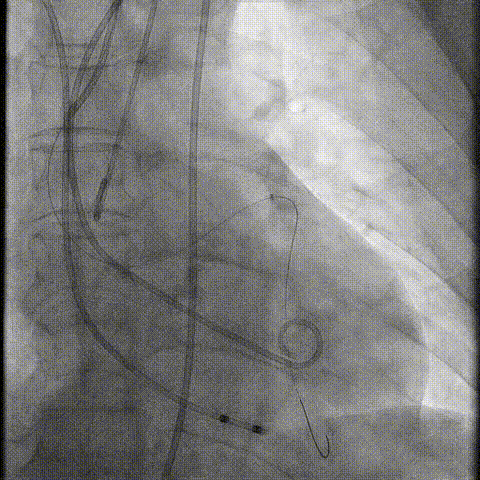

冠脉造影

手术策略和器械选择

预置Telescope™导引延长导管及导丝保护左冠,

18mm球囊预扩张再次评估冠脉闭塞风险。

介入经过及结果

Telescope™+Runthrough

18mm*40mm 预扩张

预埋 Resolute Integrity 3.5*26mm

再次评估左冠开口

第一次释放

再次评估左冠开口,考虑调整瓣膜深度

回收后调整深度,再次释放

评估左冠开口

左冠开口切线位造影

决定左冠烟囱支架保护冠脉

调整支架位置

释放冠脉支架

释放瓣膜

造影评估

支架内后扩张

根部造影